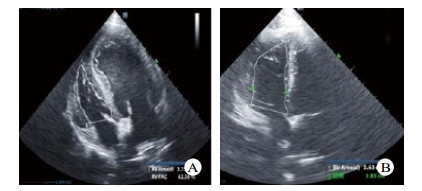

| A、B中细白线勾勒图形为右室切面内腔面积大小比较,与A图比较,B图右心室腔显著扩张 图 3 造模前后犬心脏心尖四腔心超声切面 Fig 3 Comparison of echocardiography before and after modeling |